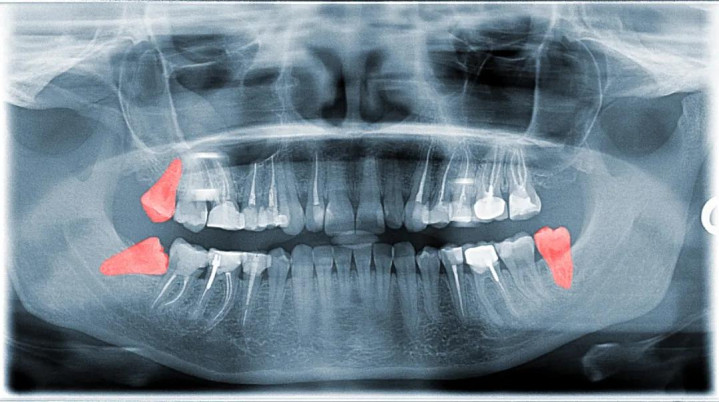

智齿早查验:许多智齿长歪,在没发炎时就应拍片查验,听从医师提倡决定是否撤废。